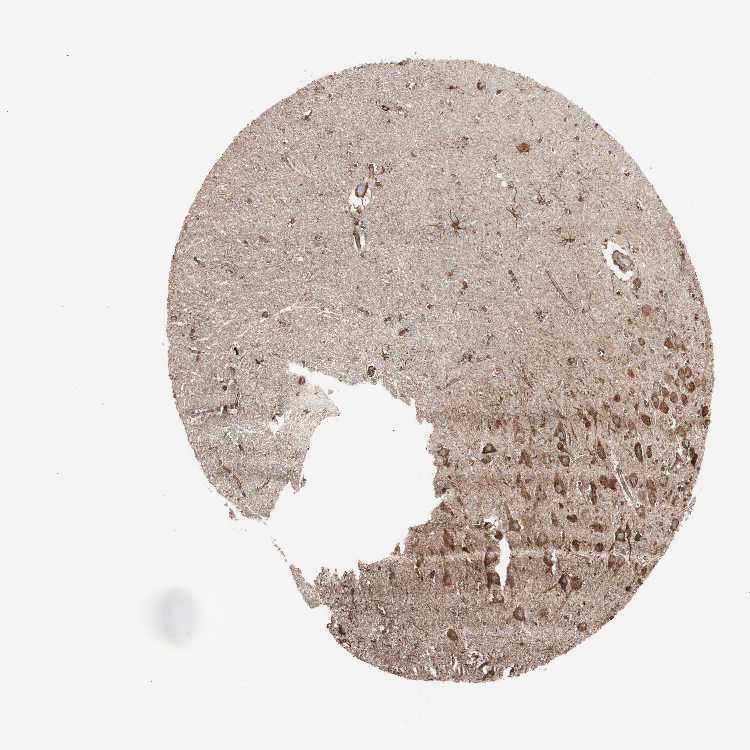

TISSUE PRIMARY DATA HIPPOCAMPUS Show tissue menu

HIPPOCAMPUS - Antibody stainingi

Antibody staining in the annotated cell types in the current human tissue is reported as not detected, low, medium, or high, based on conventional immunohistochemistry profiling in selected tissues. This score is based on the combination of the staining intensity and fraction of stained cells.

Each image is clickable and will lead to virtual microscopy that enables deeper exploration of all samples and also displays staining intensity scores, fraction scores and subcellular localization as well as patient and tissue information for each sample.

Antibody HPA069116Antibody CAB005429Antibody CAB039240Antibody CAB069907

Glial cells MediumMediumNot detectedLow

Neuronal cells MediumHighMediumMedium